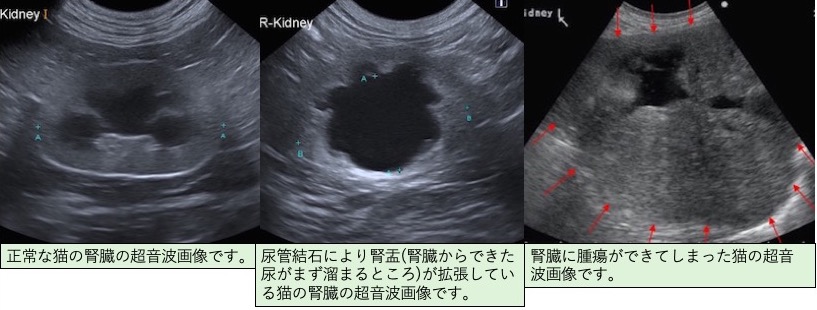

このように、「腎機能の低下」といっても原因病態(尿路結石、尿路感染症、腫瘍など)が存在することがあり、その病態に対して早期に治療することが、腎臓へのダメージを最小限にすることにつながります。

そのため、慢性腎臓病を正確に診断するためには、様々な検査(血液検査、尿検査、レントゲン検査、超音波検査、血圧測定、腎生検など)を組み合わせて行う必要があります。